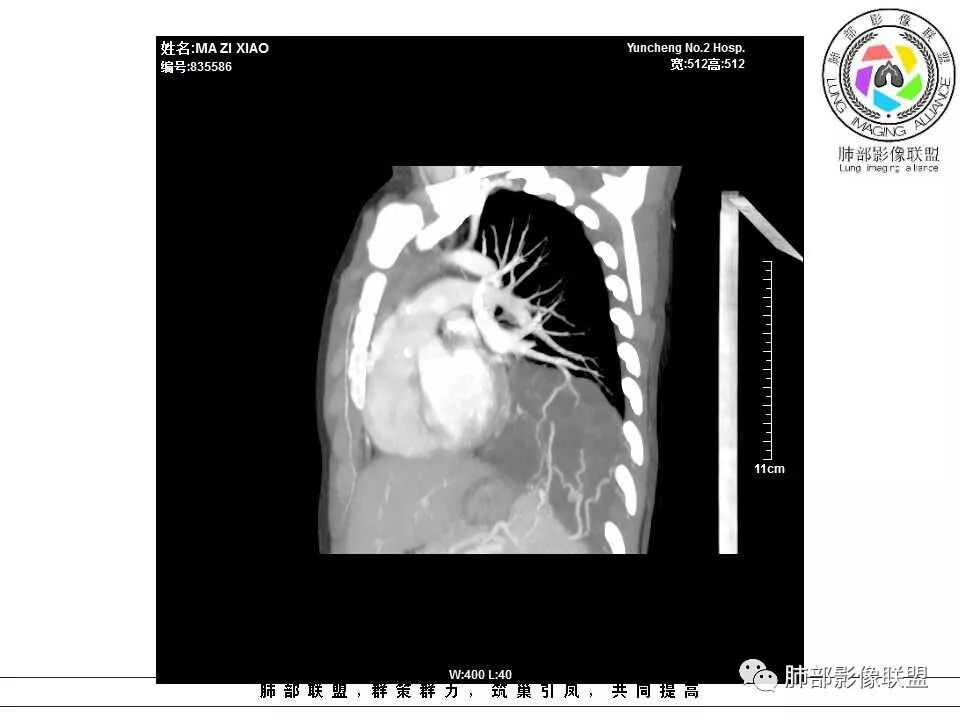

电话随访,患者在西安某医院手术,为肺隔离症,供血两支动脉,均来自腹主动脉,引流入肺静脉。

一、隔离症的血管

1.有体循环供血动脉

2.并无伴行静脉,回流到纵隔的血管不容易见到

3.相应流量的静脉,在隔离症周围通常仅有肺静脉

4.供血动脉形态有改变,常有扩张及退变